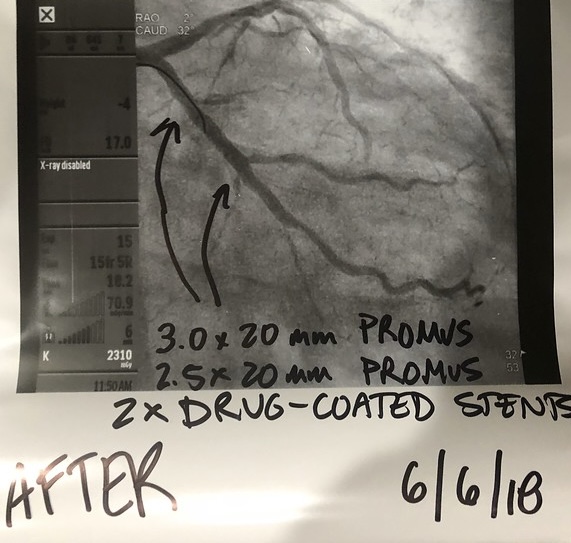

Surgeon wants to put in a couple of stents and look around to see what else he can fix....